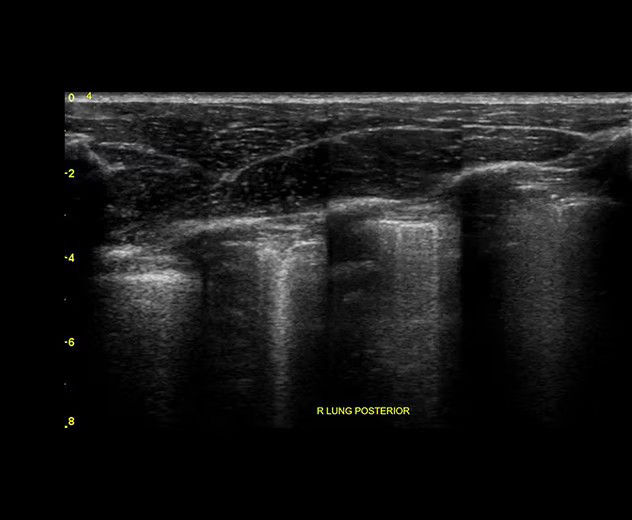

Visualize the entire lung with Lung Sweep

Lung Sweep provides a dynamic panoramic view of the entire lung. It activates when the probe taps the body and deactivates when the probe is lifted, so there’s no need to touch the screen.